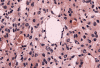

Clinical information The patient was a 54 year-old woman with a history of diabetes. She developed vomiting and frontal headache for two days. As per the descriptions of her family members, she had a few episodes of starring into the left and was unresponsive. The patient described that she could remember all these episodes clearly. On physical examination, the patient was well oriented and alert. There was no weakness in the extremities, ophthalmoplegia, diplopia, reduced visual acuity or facial weakness. An MRI and a CT scan were performed and yielded the following representative images. A surgery was performed. Representative photographs of the specimen are illustrated below.

T1-weighed MR images demonstrate an extraaxial, dural based mass involving the right supraorbital region  (Panel A and B). The mass shows homogeneous enhancement  (Panel C). CT scan demonstrates as well as rim calcification (Panel E). On T2-weighed imagers, significant vasogenic edema is demonstrated despite the small size of the lesion and the extraaxial location (Panel D).

Histologic findings on  formalin fixed, paraffin sections of the specimen are very similar to that of the frozen sections (Panel K and L). The pseudonuclear inclusions are much better visualized in the paraffin section (Panel M). The core material in the microcysts is strongly PAS positive (Panel N). The tumor cells are focally positive for cytokeratin AE1/AE3 (Panel O) and positive for epithelial membrane antigen (EMA) (Panel P). Also unique to secretory meningioma is focally positive for carcinomembryonic antigen (CEA) (Panel Q).